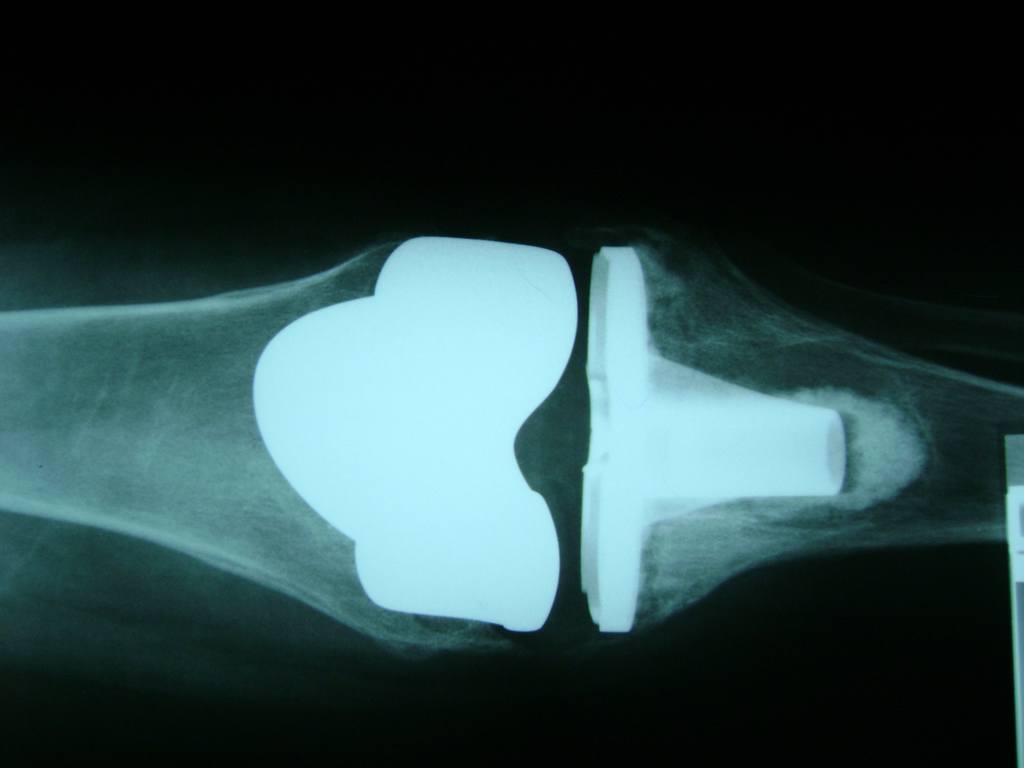

Cirugías de Peroné y Tibia

La artroscopia de rodilla es un cirugía en el cual la estructura interna de la articulación es examinada ya sea para realizar un diagnostico o para realizar un tratamiento, este procedimiento se realiza utilizando un instrumento parecido a un pequeño tubo llamado artroscopio.